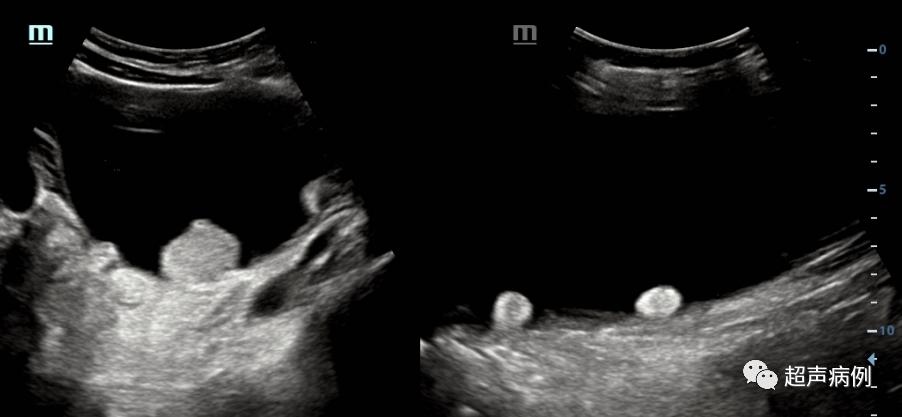

腹盆腔内已出现大小约40.3x29.3x16.0cm的巨大占位性病变。此时,我不由的感叹,常规体检,到底应设置到什么年龄?小学?还是初中?还是。。。

超声检查为一个巨大的囊性占位。

病理诊断为:交界性粘液性囊腺瘤,灶区癌变,高分化粘液腺癌形成。

最后临床诊断:右卵巢高分化粘液性腺癌ⅠA期